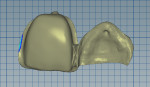

The lingual aspect of tooth No. 9 was reduced slightly and a lingual dimple was formed. An impression was taken with polyvinyl siloxane (Reprosil®, Dentsply Sirona, dentsplysirona.com), and the laboratory fabricated a stone model from the impression. The preparations on the model and wax-up were scanned to create an STL file for milling (Figure 3 through Figure 5). The laboratory milled the bridge from a commercial zirconia puck (DLMS-Crystal® Zirconia, Digital Dental, digitaldental.com). Adequate cement space was created.

The bridge was sent back to the laboratory for porcelain and staining to match the adjacent central incisor (Figure 8). It was tried in on the model (Figure 9) and then intraorally. The fit and occlusion of the bridge were verified, and the patient and parent gave their approval. The bridge was cleaned with a universal cleaning paste (Ivoclean, Ivoclar Vivadent, ivoclarvivadent.com) to remove possible salivary contamination and then re-etched (Figure 10). The abutment tooth was cleaned with chlorhexidine 2% with 70% ethanol (Consepsis™ Scrub, Ultradent, ultradent.com), rinsed, and dried, and then 37% phosphoric acid was applied for 20 seconds (Figure 11) and then rinsed and dried. An adhesive primer (Clearfil Ceramic Primer Plus, Kuraray, kuraraydental.com) containing the original 10-MDP (10-methacryloyloxydecyl dihydrogen phosphate) monomer was applied to the intaglio of the wing (Figure 12), and then a tooth primer (Panavia™ V5 Tooth Primer, Kuraray) was applied to the isolated tooth and left alone for 20 seconds and then air-dried for 20 seconds (Figure 13). The Panavia V5 paste was placed on the bridge wing, which was then placed in position and light-cured at the margins after initial self-cure. The insertion of the resin-bonded bridge with one wing and a pontic provided the patient with a conservative, esthetic result (Figure 14 through Figure 16).

Using the same protocol as in Case 1, this case illustrates the replacement of missing tooth No. 11 with a cantilevered zirconia bridge (Figure 17 and Figure 18).